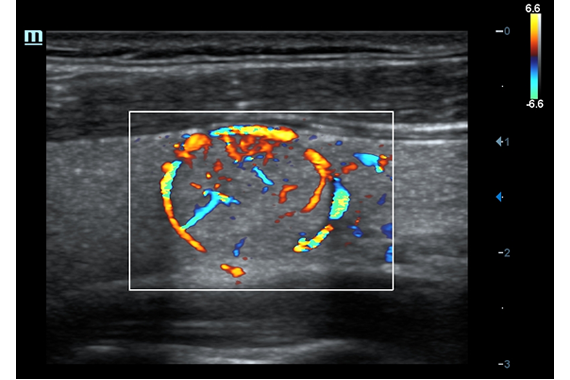

• HR Flow - режим отображения кровотока с высоким временным и пространственным разрешением для точной и однородной визуализации сосудов, в том числе самых мелких.

Трехмерная реконструкция ЦДК:

Цветовой допплер:

• Color 3D - опция получения трехмерного изображения в режиме цветового допплеровского картирования / энергетического допплера (необходим модуль 4D)

• Vascular package - предустановленные параметры, аннотации, маркеры, программы измерений для ангиологии, включая транскраниальные исследования